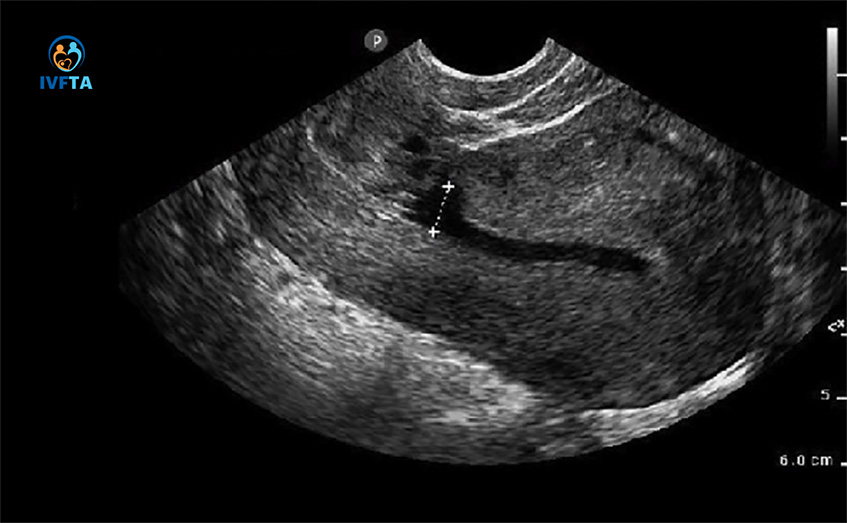

Khuyết sẹo mổ lấy thai là khu vực phản âm trống nằm tại thành trước đoạn dưới của tử cung, giữa nếp gấp của bàng quang tử cung và lỗ trong tử cung, có thể đo được ở trên hình ảnh 3 chiều. Cơ chế hình thành khuyết sẹo mổ lấy thai xuất phát từ sự mất liên tục của lớp nội mạc tử cung và một phần hoặc toàn bộ cơ của thành trước tử cung.

Hiện nay có nhiều phương pháp giúp chẩn đoán khuyết sẹo mổ lấy thai. Trong trường hợp chị em muốn thăm khám, kiểm tra tình trạng vết mổ sau sinh hoặc nghi ngờ có tụ dịch ở vết mổ cũ, bác sĩ có thể chỉ định một số phương án để chẩn đoán tình trạng này như: